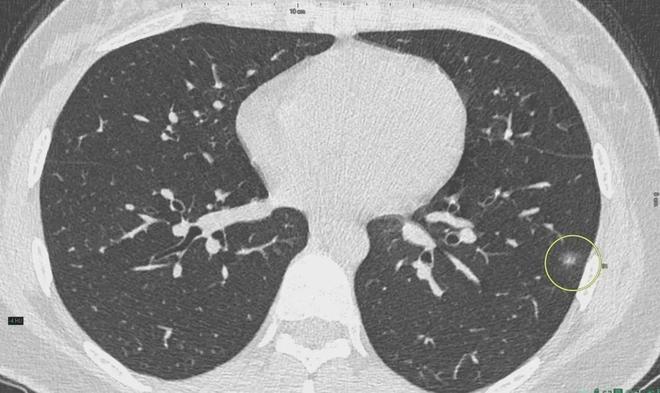

肺結(jié)節(jié)是一種常見的肺部疾病,其發(fā)病率逐年上升,雖然肺結(jié)節(jié)多數(shù)情況下是良性的,但也有可能惡化為肺癌,了解肺結(jié)節(jié)的形成原因?qū)τ陬A(yù)防和治療具有重要意義,本文將為您詳細(xì)解析肺結(jié)節(jié)的形成機(jī)制。

肺結(jié)節(jié)的形成原因

1、環(huán)境因素

環(huán)境因素是肺結(jié)節(jié)形成的重要原因之一,長期暴露于污染環(huán)境中,如空氣污染、化學(xué)污染等,可能導(dǎo)致肺部吸入有害物質(zhì),從而引發(fā)肺結(jié)節(jié),長期接觸石棉、硅塵等職業(yè)環(huán)境因素也可能增加肺結(jié)節(jié)的發(fā)病風(fēng)險。